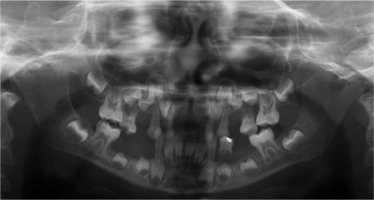

When he was 5 years of age the intraoral examination revealed incomplete primary dentition with five missing teeth, marginal gingivitis, interdental papilla hypertrophy, carious lesions in seven primary teeth, and one permanent tooth of various degrees of advancement for conservative treatment (Fig. 1). The patient was qualified for simultaneous dental treatment under general anesthesia. A panoramic radiograph picture was taken showing the advanced destruction of the alveolar bone in the maxilla and the alveolar part of the mandible. Three primary teeth were completely devoid of bone base. The roots of the lower incisors were only half of their normal length (Fig. 2). Under antibiotic protection (amoxicillin with clavulanic acid at a dose of 30 mg/kg), professional removal of dental plaque and conservative treatment of teeth extraction of four primary teeth with complicated caries and periodontitis were performed. The patient was provided with permanent dental care.